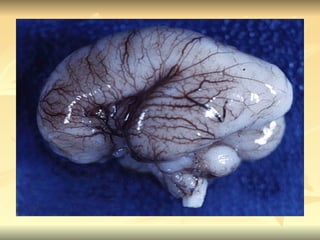

Prosencéfalo = porção frontal do cérebro Controle da sensação, percepção, emoção, aprendizagem, pensamento e outras funções intelectuais  -- bulbo; tratos olfativos, hemisférios cerebrais, gânglios nasais, tálamo, tratos ópticos, hipotálamo Mesencéfalo = porção intermediária do cérebro que une o tronco cerebral ao prosencéfalo e serve de passagem aos estímulos aferentes e eferentes Envolvido em certas funções de processamento sensorial, atenção e excitação básica Robencéfalo = porção posterior do encéfalo que envolve o quarto ventrículo

PROSENCÉFALO Diencéfalo – desenvolve-se em torno do terceiro ventrículo estruturas que sintetizam informações sensoriais e regulam  comportamento motivado incluindo tálamo e hipotálamo Telencéfalo – cérebro novo; envolve os ventrículos laterais  regulação de respostas superiores como cognição e a previsão.

Robencéfalo ou tronco encefálico se divide em: Metencéfalo = cérebro transverso Mieloencéfalo = cérebro espinhal  Controle do movimento em geral, do equilíbrio e de algumas funções  vegetativas

Prosencéfalo = porçãofrontal do cérebro Controle da sensação, percepção, emoção, aprendizagem, pensamento e outras funções intelectuais -- bulbo; tratos olfativos, hemisférios cerebrais, gânglios nasais, tálamo, tratos ópticos, hipotálamo Mesencéfalo = porção intermediária do cérebro que une o tronco cerebral ao prosencéfalo e serve de passagem aos estímulos aferentes e eferentes Envolvido em certas funções de processamento sensorial, atenção e excitação básica Robencéfalo = porção posterior do encéfalo que envolve o quarto ventrículo

PROSENCÉFALO Diencéfalo –desenvolve-se em torno do terceiro ventrículo estruturas que sintetizam informações sensoriais e regulam comportamento motivado incluindo tálamo e hipotálamo Telencéfalo – cérebro novo; envolve os ventrículos laterais regulação de respostas superiores como cognição e a previsão.

Robencéfalo ou troncoencefálico se divide em: Metencéfalo = cérebro transverso Mieloencéfalo = cérebro espinhal Controle do movimento em geral, do equilíbrio e de algumas funções vegetativas